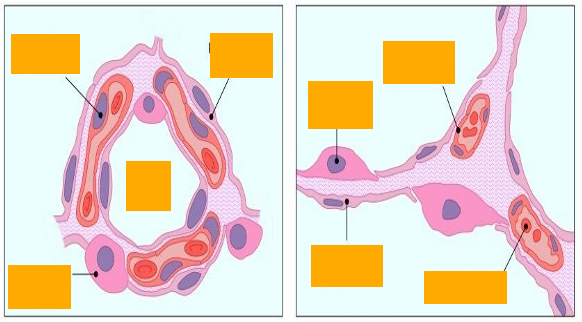

Alveolar epithelium

Type II pneumocyte

Identify labeled cell, sites and one specific feature?

Clara cell , mucosa of bronchiole, dome shaped apical surface and secretory granules

A -Identify the cell

B -Identify the labelled structure

A- pneumocyte type II

B- Lamellar bodies

Lung alveoli and interalveolar septea